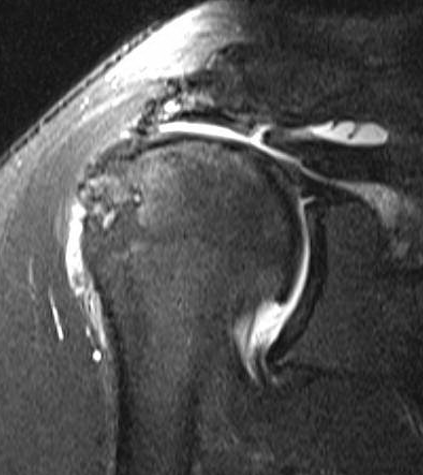

MRI

Measure tear in the coronal and sagittal plane

Massive rotator cuff tear of the supraspinatus and infraspinatus tendon - retracted to glenoid

MRI predictors of reparability

- 60 patients with large and massive tears

- irreparability associated with retraction to or beyond glenoid

- irreparability associated with tangent sign / advanced fatty infiltration / superior migration humeral head

- 120 patients with large and massive tears

- irreparability associated with modified grade III Patte (retraction to medial 5th humeral head)

- associated with 94% chance or irreparability

- irreparability also associated with reduce acromiohumeral distal / superior migration humeral head

Examples of rotator cuff tears that are likeley irreparable